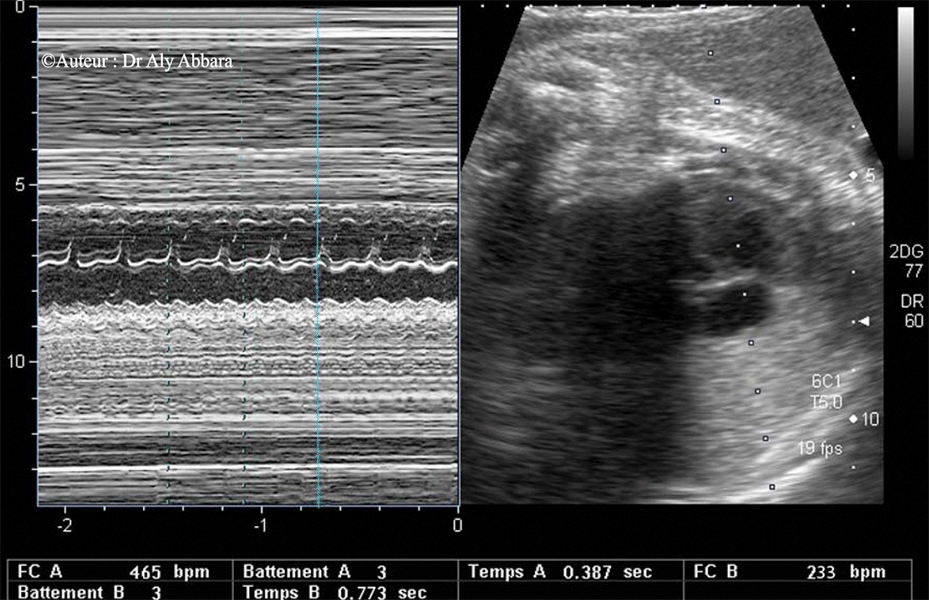

Mode-M

Flutter auriculo-ventriculaire

Analyse du spectre mod-M

Flutter auriculo-ventriculaire - détails

• Chez le fœtus, le flutter auriculaire se caractérise par une fréquence auriculaire supérieure à la fréquence ventriculaire.

• La fréquence auriculaire varie de 300 à 600 bpm ; elle est régulière.

• Le bloc auriculo-ventriculaire est variable :

• Quand il s'agit d'un bloc auriculaire de type "2:1", la fréquence ventriculaire est régulier et égale à la moitié de la fréquence auriculaire.

• Quand il s'agit d'un bloc auriculo-ventriculaire variable, il résulte une fréquence ventriculaire irrégulière de l'ordre de 150 à 250 bpm et un bloc auriculo-ventriculaire allant de 2:1 à 4:1.